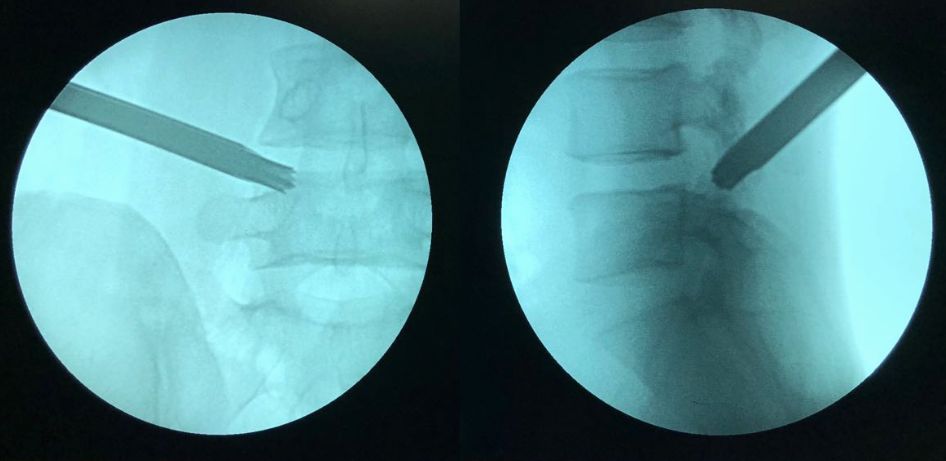

portant; word-wrap: break-word !important;">5.?靶點(diǎn)穿刺:使用 1 mm 的導(dǎo)絲插入 18 G 穿刺針,使用逐層套筒逐級(jí)擴(kuò)大切口,直到使用能通過(guò) 2.5 mm 克氏針的套管。然后使用直徑 2.5 mm 的克氏針精確穿刺于與目標(biāo)椎間隙相對(duì)的上關(guān)節(jié)突的腹側(cè)??梢韵茸尶耸厢樳M(jìn)入椎間孔,再向背側(cè)滑向上關(guān)節(jié)突腹側(cè)(Walking 技術(shù))。通過(guò)透視,調(diào)整克氏針的位置。

portant; word-wrap: break-word !important;">8.?撥出環(huán)鋸,插入鉛筆芯和內(nèi)鏡外套管,術(shù)中透視觀察內(nèi)鏡外套筒是否正對(duì)椎間盤(pán)突出的位置,常位于神經(jīng)根管盤(pán)黃間隙的位置。